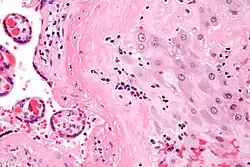

Micrograph of a chronic deciduitis, showing the characteristic plasma cells. H&E stain. |

Chronic deciduitis is a type of long-lasting inflammation that arises in pregnancy and affects the endometrial stromal tissue (decidua).

It is associated with preterm labour.[1] The diagnosis rests primarily on the presence of plasma cells.[2]